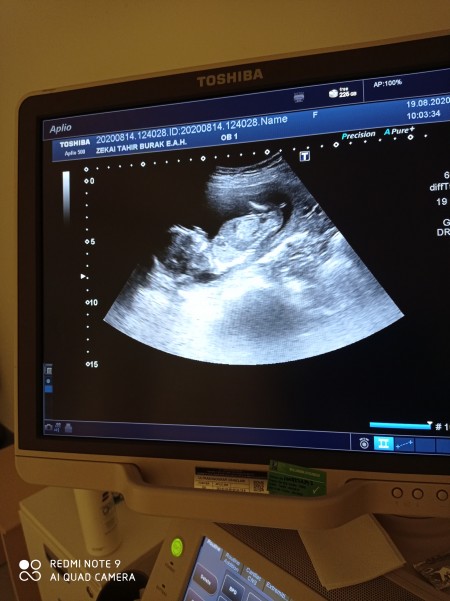

Kızlar bı önceki gittiğimde doktorum ciğerleri parlak gibi dedi 2li testimin sonucuna baktı sonucunda iyi dedi sizce bebeğimde bı sıkıntı oluşur mu sonradan ?

image